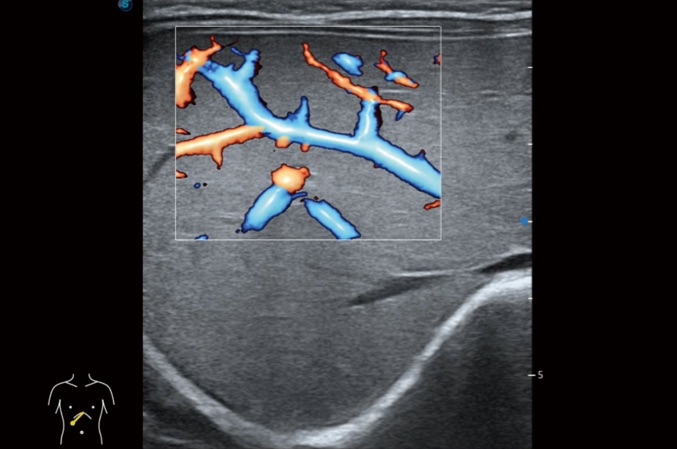

高分辨率血流成像技術(shù)提高了對低速血流信號(hào)的檢測能力。在提高空間分辨率的同時(shí),也克服了血流外溢現(xiàn)象,為用戶提供更加真實(shí)的血流動(dòng)力學(xué)信息。

心血管應(yīng)用